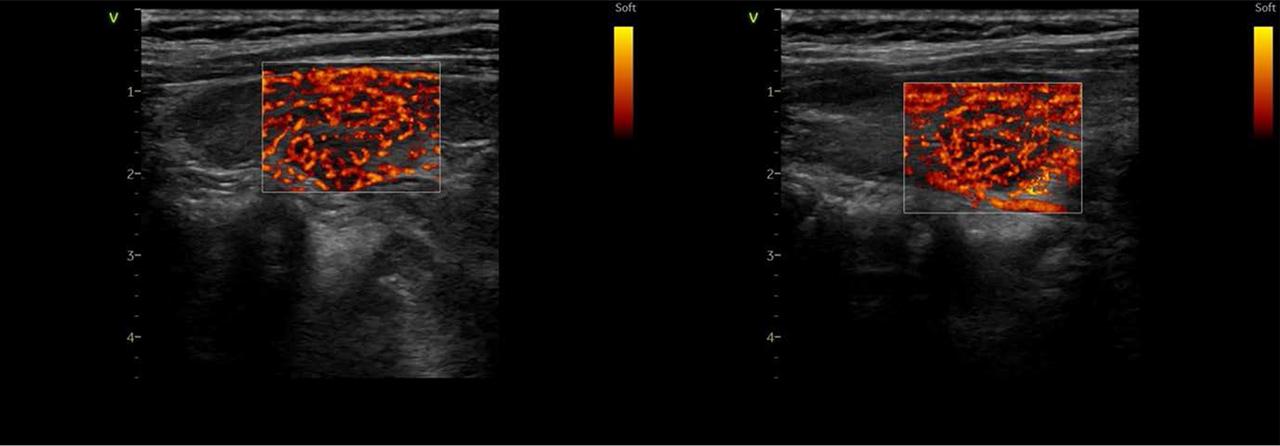

FIGURE 2.